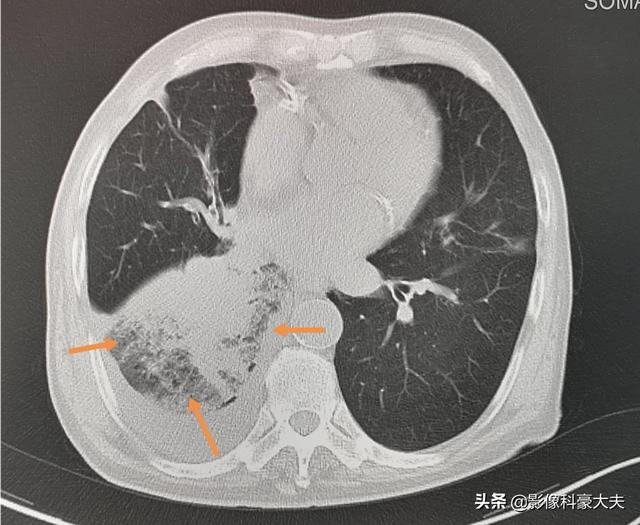

2.二次感染

肺がん患者は免疫力が低下しているため、気道が狭くなり、通常、閉塞性肺炎を引き起こし、時には命にかかわることもある。

これは79歳の男性で、4年前から小細胞肺がんを患っている。右下葉の気管支が狭くなっているため、閉塞性肺炎を引き起こし、高熱を繰り返す。

2.肺感染症

一方では、進行した肺癌患者は、腫瘍が気管を圧迫し管腔を閉塞するため、痰をスムーズに排出できないことがある。他方、進行肺癌患者は消費量が増加し、食欲が低下するため、栄養不良や免疫力の低下を招く可能性がある。これらはいずれも肺内感染を引き起こしやすい。